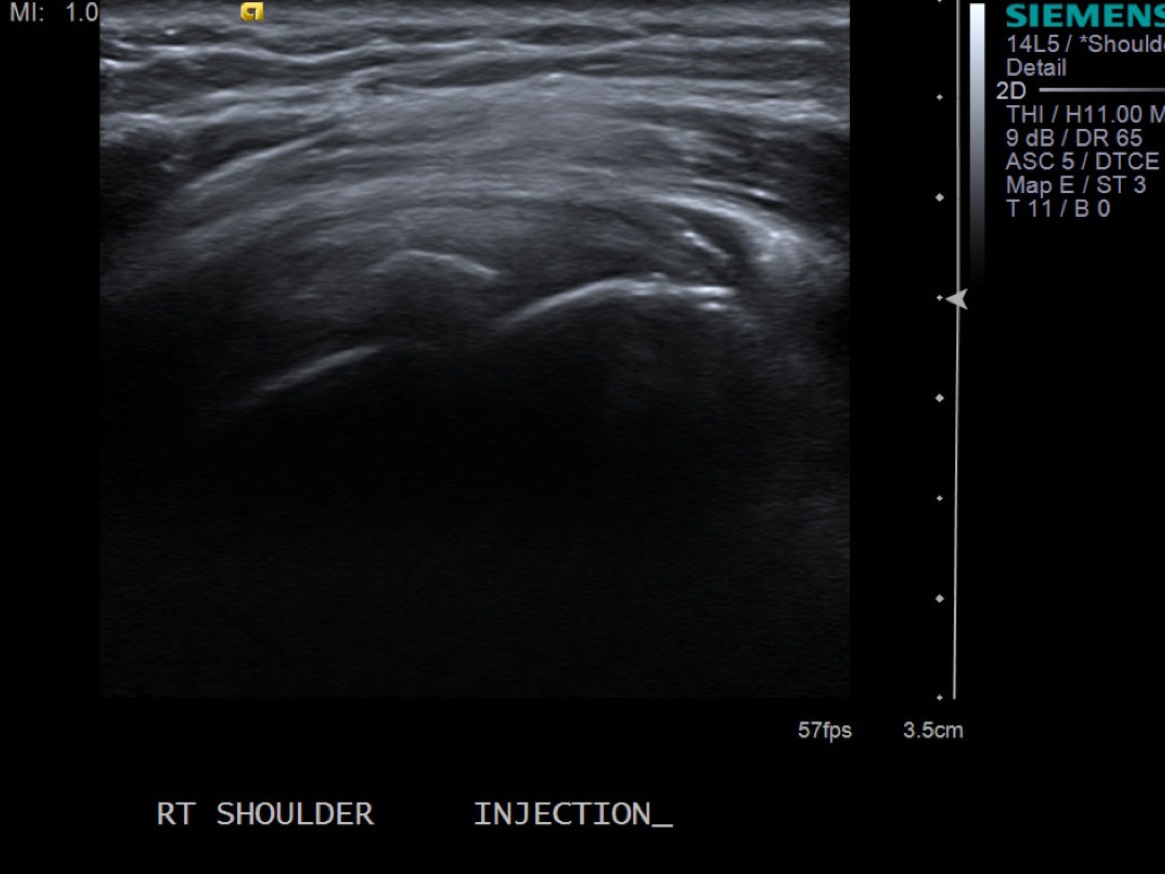

• descriptiondescription

Short axis view of supraspinatus tendon with calcific deposit